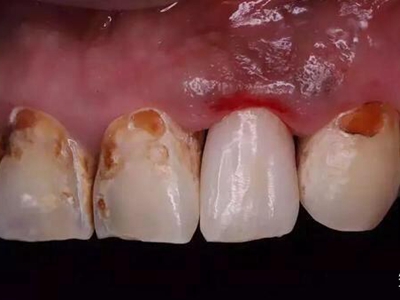

酸蚀症牙齿多处缺损发黄图

酸蚀症患者的牙齿会出现多处缺损,牙根部有不规则骨质剥脱,周围发黄,牙前侧也出现坑洼及大块缺损,使牙列不平整,可进行脱敏、修复治疗等。